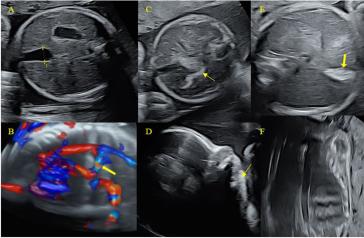

Chorio-amniale Separation bei einem Feten mit restriktiver Dermatopathie

Das Amnion und das Chorion fusionieren mit dem Beginn des zweiten Trimenons zur eigentlichen Fruchtblase. Die Chorionhöhle obliteriert somit kontinuierlich und sollte mit 14 bis 16 Wochen verschwunden sein. Eine chorio-amniale Separation (CAS) kann sekundär oder primär auftreten. Sekundär z. B. nach invasiven diagnostischen (z. B. Amniozentese) oder therapeutisch-fetoskopischen Eingriffen. Man kann das auch gelegentlich bei Mehrlingsschwangerschaften, bei massivem Polyhydramnion und auch nach hohem Blasensprung beobachten, dann meist lokalisiert, kann sich aber auch ausdehnen zu einer vollständigen Ablösung des Amnions (1). Diese sekundären Formen einer CAS kann man sich somit gut erklären. Die primären sind indes etwas komplexer. Meines Erachtens sind sie als Ausdruck einer grundlegenden Störung der extrazellulären Matrix (ECM) zu verstehen. Tatsächlich wird eine primäre CAS gelegentlich bei Trisomie 21, 18 und 13 beschrieben. Diese Trisomien gehen mit einer Reifungsstörung der ECM einher, welche auch die pathologische Nackentransparenz erklärt (2, 3). Aber auch bei Fällen mit restriktiven Dermatopathien (RD) wurden CAS beschrieben (4). Diese Beobachtungen unterstreichen die Tatsache, dass sowohl das Amnion wie die Haut ektodermalen Ursprungs sind. Ja, unser Fall entpuppte sich erst nach Geburt als ein Kind mit einer leider letalen RD. Der primäre Pathomechanismus dieser Störungen ist weiterhin wenig geklärt. Aber ähnlich den Veränderungen der ECM bei den Trisomien ist bei den Fällen mit RD die Haut charakterisiert durch eine abnorme Akkumulation von Kollagenen und fehlenden elastischen Fasern. Es sind seltene, autosomal rezessive (seltener dominante) Mutationen klinisch charakterisiert durch eine dünne, durchscheinende und rigide Haut (Bild 1), mit Gesichtsdysmorphien (kleine Nase und kleiner Mund, Micrognathie, tiefsitzende Ohren, weite Fontanellen) und multiple Gelenkskontrakturen neben Wachstumsrestriktion und auch sonstige Skelettauffälligkeiten (Bild 2, 3) (5). In unserem Fall wurde eine autosomal rezessive Mutation im ZMPSTE24-Gen gefunden. Diese Mutation führt in homozygoter Version (beide Eltern Träger!) zu diesen klinischen und morphologischen Besonderheiten (6).

Die CAS ist sicherlich auch ein Zeichen der fehlenden Elastizität des Amnions und es ist nicht erstaunlich, dass die Rate an vorzeitigem Blasensprung bei Fällen mit RD mit 57 % deutlich überrepräsentiert ist. Die meisten Fälle werden zwischen 30 und 33 Wochen geboren (7). Bedingt durch diese restriktive Haut fallen die Feten auch durch eine Hypo- bis Akinesie auf.